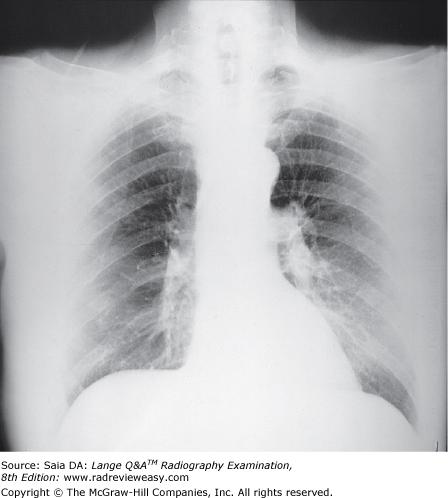

Which of the following statements is (are) true regarding the images below?

- Image A was made using a higher kilovoltage than image B.

- Image A was made with a higher-ratio grid than image B.

- Image A demonstrates shorter-scale contrast than image B.

A 1 only

B 1 and 2 only

C 2 and 3 only

D 1, 2, and 3

-Image A was made using 80 kV at 75 mAs; image B was made using 100 kV at 18 mAs; all other exposure factors remained the same. As kilovoltage is increased, the percentage of scattered radiation relative to primary radiation increases—hence, the grayer appearance of image B. Use of optimal kilovoltage for each anatomic part is helpful in keeping scatter to a minimum. The production of scattered radiation also will be limited if the field size is as small as possible. A grid is the most effective way to remove scattered photons from those exiting the patient. Grids are designed to selectively absorb scattered radiation while absorbing as little of the useful beam as possible. Images produced with higher-ratio grids are likely to evidence the effect of less scattered radiation than those made with lower-ratio grids.

Which of the following statements is (are) most likely true regarding the figure below?

1.Image A was made using a higher kVp than image B.

2.Image A was made with a higher ratio grid than image B.

3.Image A demonstrates shorter scale contrast than image B.

-Image A was made using 80 kVp at 75 mAs; Image B was made using 100 kVp at 18 mAs; all other exposure factors remained the same. As kVp is increased, the percentage of scattered radiation relative to primary radiation increases, hence the grayer appearance of image B. Use of optimal kilovoltage for each anatomic part is helpful in keeping scatter to a minimum. The production of scattered radiation will also be limited if the field size is as small as possible. A grid is the most effective way to remove scattered photons from those exiting the patient. Grids are designed to selectively absorb scattered radiation while absorbing as little of the primary radiation as possible. Images produced with higher ratio grids will possess fewer grays than those made with lower ratio grids.